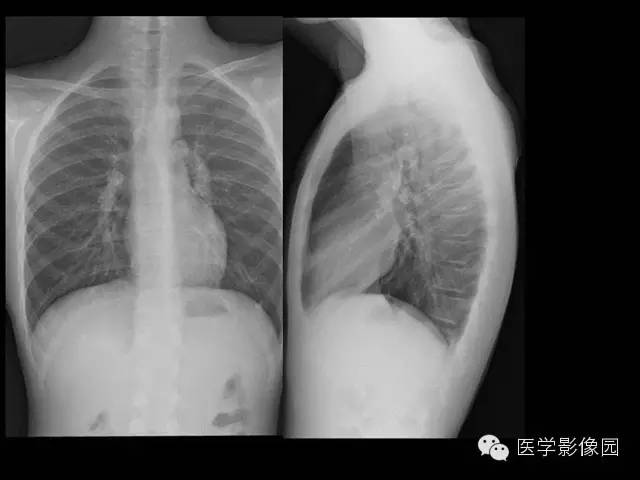

【病例】组织胞浆菌病1例CT影像表现

X线检查、CT:可见肺、肝、脾等脏器可有许多钙化点。纵隔组织胞浆菌病还包括纵隔的肉芽肿和纤维化性纵隔炎。组织胞浆菌病大多数不需要特殊治疗,通常经过卧床休息、加强营养等支持疗法后,多在3个月至数年间自然痊愈。